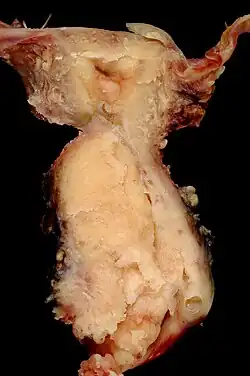

Pathologie

Die Mehrheit aller invasiven Zervixkarzinome sind Plattenepithelkarzinome (80 Prozent), gefolgt von den Adenokarzinomen (5–15 Prozent). Bevorzugter Entstehungsort ist die sogenannte Transformationszone, in welcher das Plattenepithel der Portio auf das Zylinderepithel des Zervix trifft.[21] Andere Tumorformen, wie Adenokankroide, adenosquamöse und mukoepidermoide Karzinome, sind selten. Als Besonderheit treten, ebenfalls selten, sogenannte Gartnergangkarzinome auf. Sie gehen vom Gartnerschen Gang, einem kleinen Teil des rückgebildeten Wolffschen Ganges, aus. Da sich dieser Tumortyp in der Tiefe entwickelt und erst im Verlauf in den Gebärmutterhalskanal durchbricht, hilft die übliche Früherkennung hier nicht.[20] Sarkome der Gebärmutter können sehr selten auch die Zervix befallen.[22] Eine Sonderstellung nehmen dabei die Müllerschen Mischtumoren ein, bei denen karzinomatöse und sarkomatöse Komponenten im gleichen Tumor auftreten. Auch sie befallen eher den Gebärmutterkörper als die Zervix.[23]